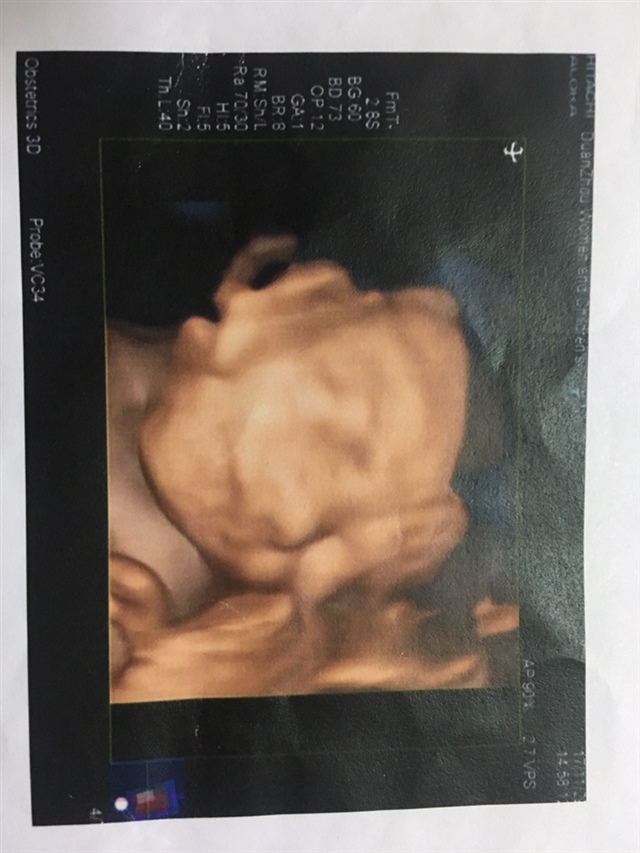

宝宝3个月2天

男

我猜是男孩吧

💓 所谓伊人*:男